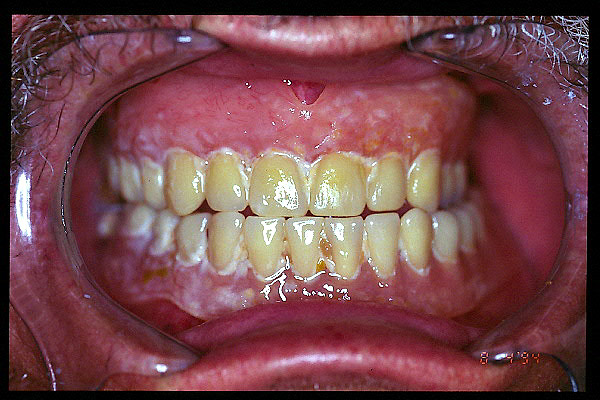

CM Enfermedad periodontal avanzada